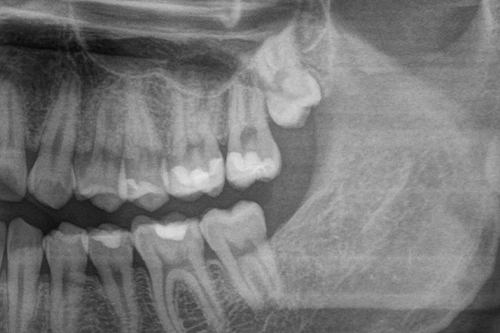

「痛みがないから抜かないでいい」と考えていても、レントゲンを撮ると隣の歯が溶けていた、というケースも少なくありません。抜かないまま放置するリスクを知るためにも、定期検診でのレントゲン確認が早期発見・早期対応につながります。

斜めに生えた親知らずのパノラマレントゲン

ただし、抜歯の難易度は生え方によって大きく異なります。まっすぐ生えている場合は比較的短時間で終わることが多いですが、横向きや骨の中に深く埋まっているケース(埋伏歯)では、歯茎の切開・骨の調整・歯の分割などが必要になる場合があります。下記は一般的に知られている難易度の目安です。

歯茎の切開や歯の分割が必要になることが多く、術後の腫れや痛みも出やすいとされています。事前のCT検査による確認が重要です。

骨の中に完全に埋まった親知らず(抜歯前レントゲン)

完全埋伏

(骨の中に完全に埋まっている)

骨を大きく削る必要があり、神経への影響リスクが高い場合は大学病院等での対応が適切とされることがあります。

※処置時間はあくまで目安です。歯の形状・骨の状態・個人差によって大きく異なります。神経(下歯槽神経)に近い位置にある親知らずの場合、ごくまれに術後一時的な感覚の変化(麻痺)が生じることがあります。麻痺や出血のリスクが高い場合は万が一に備え、大学病院等での抜歯が推奨されます。不安な点は事前に担当医にご確認ください。